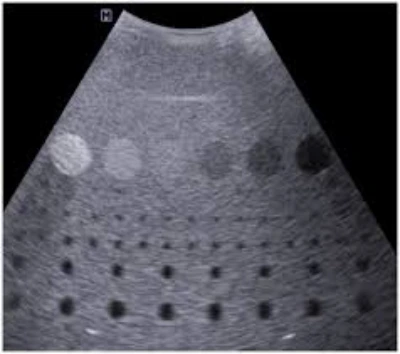

Calibração de aparelho de ultrassom

Entenda a Importância da calibração de aparelho de ultrassom!

A calibração de aparelho de ultrassom é um procedimento técnico que ajusta componentes eletrônicos e mecânicos para assegurar precisão nas imagens obtidas durante exames.

A calibração de aparelho de ultrassom envolve a verificação e ajuste de parâmetros como frequência, amplitude e tempo de resposta do equipamento .

Esses ajustes promovem que as imagens geradas sejam precisas e confiáveis, permitindo uma interpretação correta por parte dos profissionais de saúde.